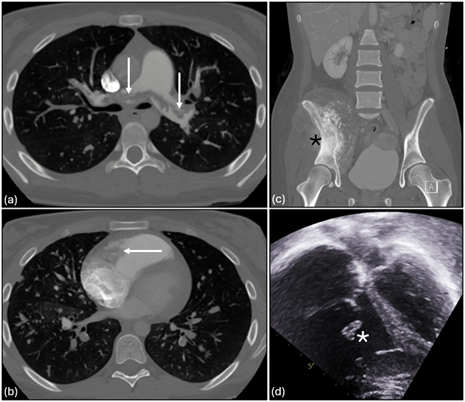

A key question with the Alterra Prestent and 29-mm SAPIEN 3 valve is what approach is optimal for repeated valve-in-valve (VIV) therapy. Current practice assumes each successive valve must be smaller, potentially limiting future options rather than considering the potential for frame overexpansion. To assess this, we evaluated over-expansion capabilities with serial VIV implants using benchtop (Figure 1) and in vivo sheep models. Over-expansion was achieved using a 2-balloon technique, inflating side-by-side 18-mm and 20-mm Atlas Gold balloons (BD) to 14 atmospheres, followed by circularization with a 28-mm True dilation balloon (BD) at 12 atmospheres followed by valve implantation. Repeat implantation of a 29-mm SAPIEN valve was then performed and the process was repeated. Post-implantation measurements confirmed that the desired specifications were still achieved after 4 total 29-mm SAPIEN 3 implants were placed in this manner (Figures 2 and 3).